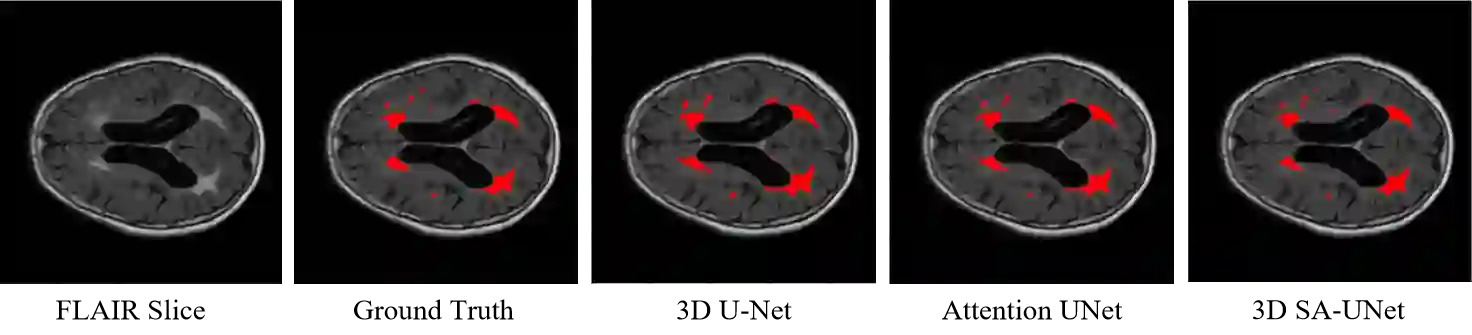

White Matter Hyperintensity (WMH) is an imaging feature related to various diseases such as dementia and stroke. Accurately segmenting WMH using computer technology is crucial for early disease diagnosis. However, this task remains challenging due to the small lesions with low contrast and high discontinuity in the images, which contain limited contextual and spatial information. To address this challenge, we propose a deep learning model called 3D Spatial Attention U-Net (3D SA-UNet) for automatic WMH segmentation using only Fluid Attenuation Inversion Recovery (FLAIR) scans. The 3D SA-UNet introduces a 3D Spatial Attention Module that highlights important lesion features, such as WMH, while suppressing unimportant regions. Additionally, to capture features at different scales, we extend the Atrous Spatial Pyramid Pooling (ASPP) module to a 3D version, enhancing the segmentation performance of the network. We evaluate our method on publicly available dataset and demonstrate the effectiveness of 3D spatial attention module and 3D ASPP in WMH segmentation. Through experimental results, it has been demonstrated that our proposed 3D SA-UNet model achieves higher accuracy compared to other state-of-the-art 3D convolutional neural networks.